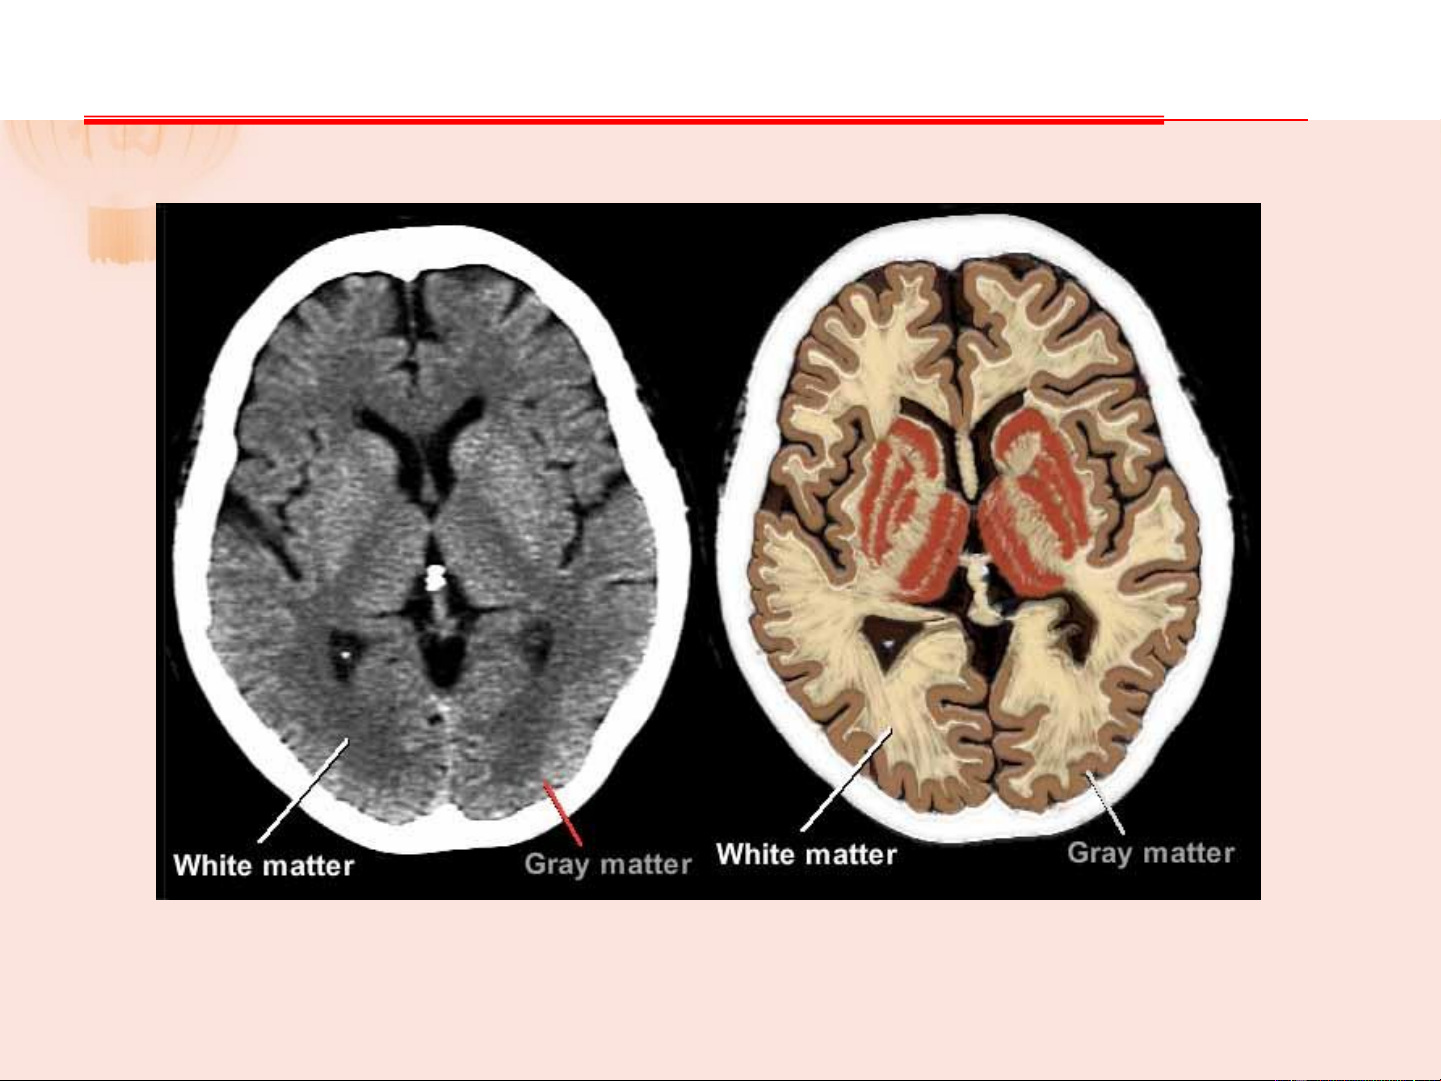

- Gồm nơron và mô TK đệm chống đỡ, mạch máu, gần như không có MLK - Chia thành 2 phần:

+ Chất xám: thân nơron và sợi TK trần, tập trung

ở vỏ não, nhân xám dưới vỏ, trung tâm tủy sống.

+ Chất trắng: tập trung các sợi TK, phần lớn là có myelin 1.1. TỦY SỐNG Chất xám: Chất trắng: Gồm thân các nơron Gồm các sợi TK có đa cực, TBTK đệm, sợi myelin (do tb ít nhánh bao TK không myelin, một ít bọc) và TBTK đệm sợi có myelin mảnh, mạch máu 1.1. TỦY SỐNG Chất xám: